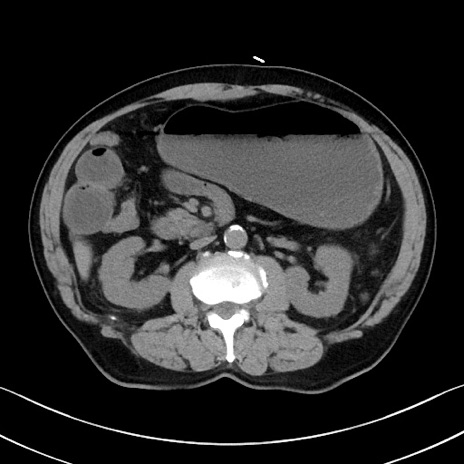

症例35(横断像)

【症例】70歳代 男性

【主訴】腹部膨満、嘔吐

【現病歴】昨日より腹部膨満感出現。本日増悪し、仙痛出現。嘔吐あり、受診。

【既往歴】糖尿病、胆摘後

【身体所見】BP 149/80mmHg、HR 74/min、BT 35.9℃、腹部:膨満、軟、圧痛なし。腸雑音減弱あり。上腹部正中切開瘢痕あり。

【データ】WBC 13500、CRP 1.72